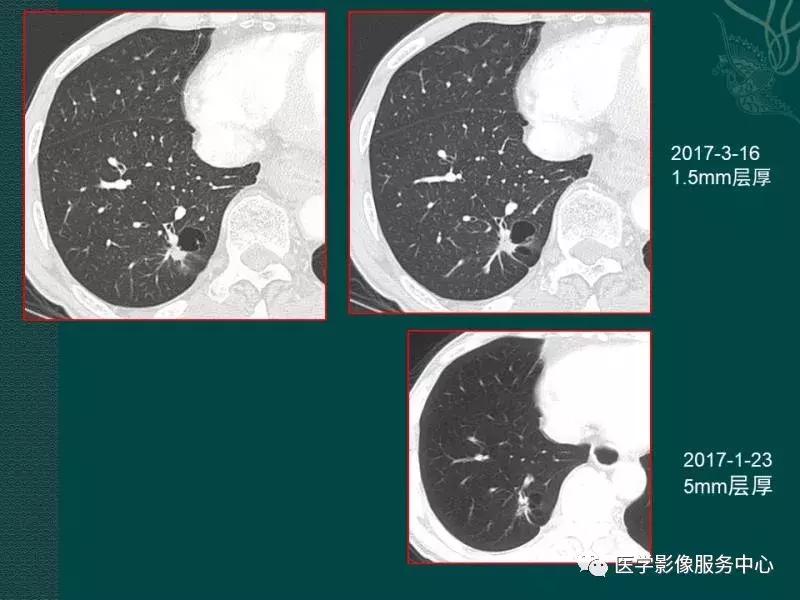

病例一

病例二

病例三